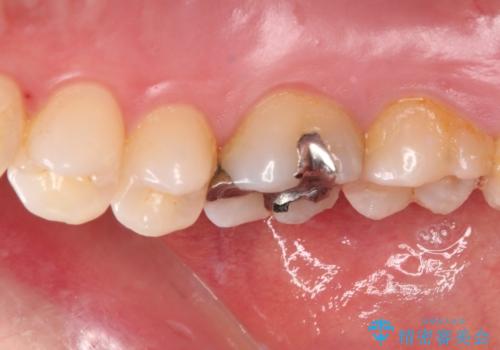

まず麻酔をして銀歯を外し、むし歯を除去し、形を整えて型取りします。

そして次の来院時、セラミックインレーを装着し、噛み合わせなどの調整を行います。